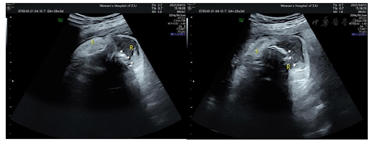

辅助检查:1.本院产前诊断超声检查示:胎位:ROA胎心:147次/分胎动:可及双顶径9.2 cm,头围32.5 cm,股骨长7.2 cm,腹围34.3 cm,胎盘:前壁GrII级,羊水指数:9.0 cm,脐动脉S/D比值2.5。备注:胎儿右侧颜面部见5.2 cm×3.9 cm×3.7 cm不均低回声,局部边界不清,内见丰富血流信号,RI:0.59;右侧上颌骨回声不规则、见回声中断,低回声与该侧上颌骨关系密切;右侧上牙槽处回声不规则、见回声中断;颈部见"U"形切迹(图1,图2,图3,图4)。诊断结果:宫内孕,单活胎,胎儿右侧颜面部不均低回声(肿瘤考虑,恶性可能),目前胎儿脐带绕颈1周。